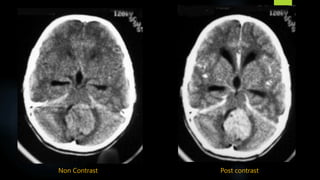

Medulloblastoma (contd.)

 CT - a heart or pear shaped hyperdense midline vermian mass abutting the roof of the fourth

ventricle, with perilesional oedema, variable patchy enhancement and hydrocephalus.

 Brainstem -displaced anteriorly.

 Cystic change, haemorrhage and calcification may be seen.

 Typical features - seen in only 30 % of cases

 Atypical features are common

- Cystic changes (65%)

- Isodense attenuation on NECT (3%) and abnormal contrast enhancement

Non Contrast Post contrast